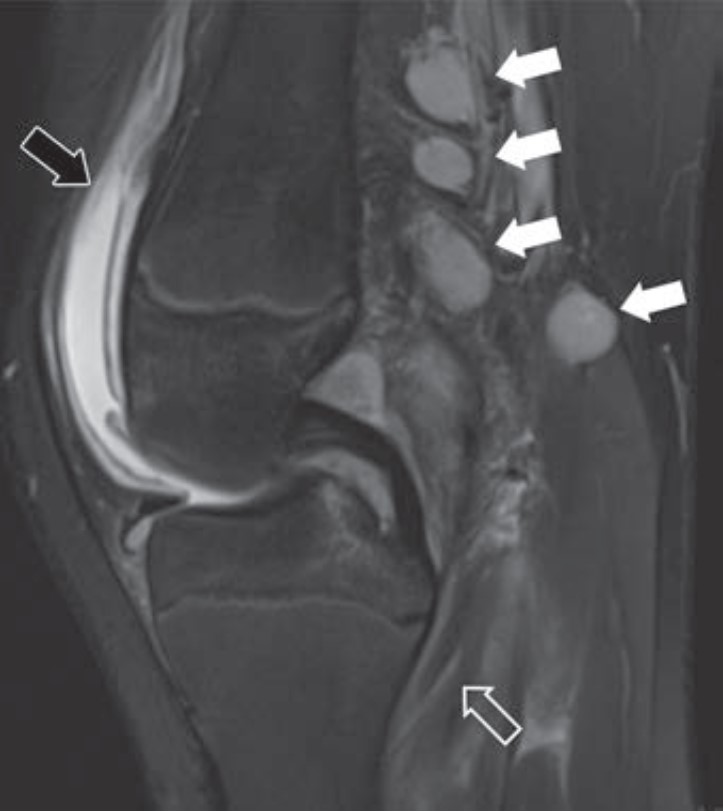

A Downward Spiral of Knee Pain and Swelling: Use of MRI to Distinguish Lyme Arthritis From Other Pediatric Arthritides

Clinical features of Lyme arthritis overlap with those of both septic arthritis and juvenile idiopathic arthritis, making the diagnosis of Lyme arthritis challenging. As “A Downward Spiral of Knee Pain and Swelling: Use of MRI to Distinguish Lyme Arthritis From Other Pediatric Arthritides” shows, MRI can help differentiate Lyme arthritis of the knee from other entities when certain imaging features, such as popliteal adenopathy, myositis, and lack of subcutaneous edema, are present. This first Roentgen Ray Review Case Report concerns a 13-year-old boy with a 1-month history of knee pain and swelling (Fig. 3).